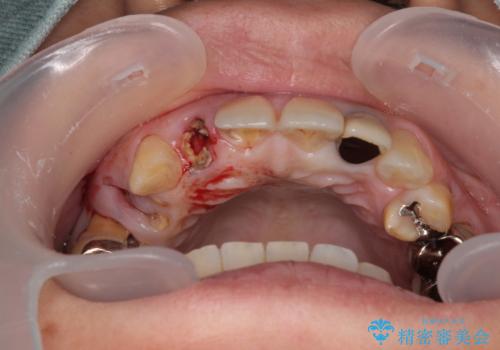

- 歯が破折しているため、抜歯が必要であると近医で診断されてからも放置を続けてしまったとのことで来院された患者様です。

臼歯はもはや咬み合わせに寄与していない状態であり、3歯を抜去してインプラント2本埋入によるブリッジ補綴を計画しました。

セオリーとしては、インプラント補綴治療により奥歯の咬み合わせを確立してから、前歯部の処置を行うことになりますが、初めてのインプラント治療であることや、前歯部の見た目が気になっていることから、前歯の抜歯即時埋入インプラントによる補綴治療を先行して行い、並行して奥歯のインプラント治療を進めて行くこととしました。

抜歯即時埋入インプラントによる補綴治療の特徴は、短期間であることや処置数が少ないことが挙げられます。また、表側の歯肉の陥凹を避けることができるというメリットがあります。しかしながら、今回は歯根破折の程度が酷く、やや膨らみを失うこととなりましたが、スムーズに治療を終えることができました。